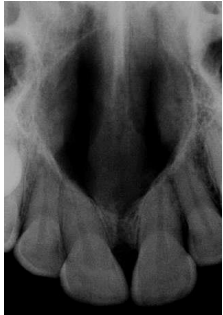

Um paciente de 24 anos, sexo feminino, procurou atendimento odontológico queixando-se de um desconforto pela tumefação da região anterior do palato. Na avaliação do exame radiográfico periapical apresentou uma imagem radiolúcida bem-circunscrita próxima ou na linha média da região anterior de maxila, entre os ápices dos incisivos centrais, sendo observado o deslocamento das raízes dos incisivos. O paciente não se queixava de dor, nem relatou história de trauma ou de procedimento cirúrgico nessa região. Observou-se que no exame clínico, os incisivos superiores se apresentavam íntegros, sendo que os testes de percussão, profundidade de sondagem e palpação na área do vestíbulo, não foram identificados sinais de anormalidades, bem como os testes de sensibilidade pulpar apresentaram -se dentro da normalidade. Ainda na inspeção observou-se uma tumefação firme assintomática, porém o paciente percebeu que ela vem aumentando de tamanho. Diante do caso acima relatado, qual o diagnóstico provável?